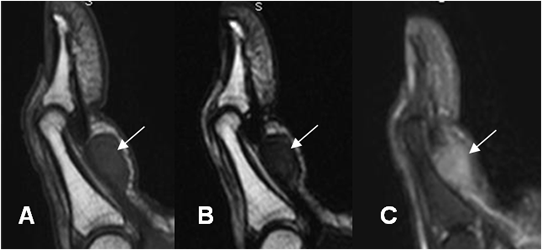

Fig 96 B. Enfermedad de Dupuytren.

A: RM sagital en T1, B: RM sagital en T2 y C: RM sagital en STIR. Deformidad en flexión del dedo, con imagen ovalada que se relaciona con el mecanismo flexor. Esta lesión es hipointensa en T1 y T2 e hiperintensa en STIR, por el componente fibroso y corresponde a enfermedad de Dupuytren.